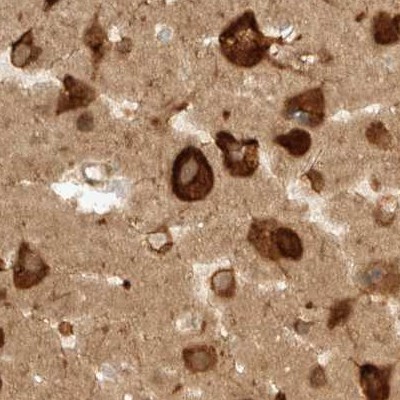

Immunohistochemistry analysis in human testis and skeletal muscle tissues using Anti-EIF4G3 antibody. Corresponding EIF4G3 RNA-seq data are presented for the same tissues.